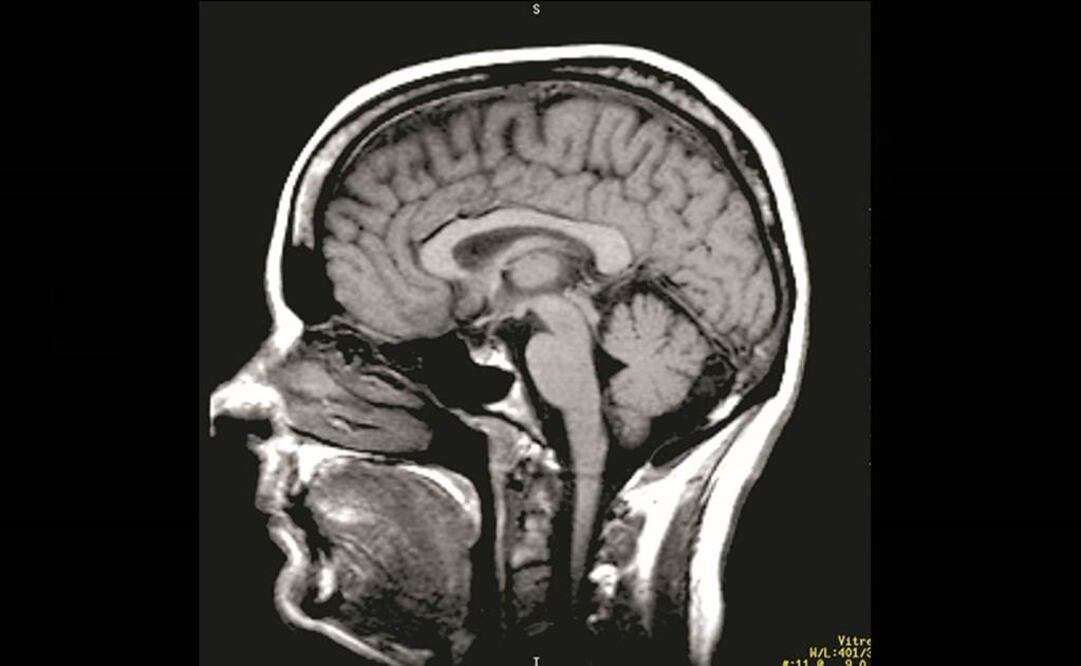

Un ruso aquejado de atrofia muscular espinal(AME), una grave enfermedad genética que ataca las neuronas motoras, quiere someterse a una pionera operación en la que su cabeza sería trasplantada a un cuerpo sano uniéndola por la espina dorsal.

El único precedente de una operación similar se produjo en 1970, cuando el doctor Robert White, de la Universidad de Medicina Case Western Reserve, trasplantó la cabeza de un simio al cuerpo de otro. Ocho días después, el animal murió.